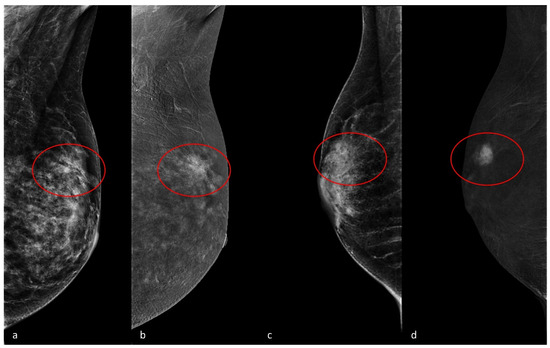

- Meucci, R.; Pistolese, C.A.; Perretta, T.; Vanni, G.; Beninati, E.; Di Tosto, F.; Serio, M.L.; Caliandro, A.; Materazzo, M.; Pellicciaro, M.; et al. Background Parenchymal Enhancement in Contrast-enhanced Spectral Mammography: A Retrospective Analysis and a Pictorial Review of Clinical Cases. In Vivo 2022, 36, 853–858. [Google Scholar] [CrossRef] [PubMed] [PubMed Central]

- Nicosia, L.; Battaglia, O.; Venturini, M.; Fontana, F.; Minenna, M.; Pesenti, A.; Budascu, D.; Pesapane, F.; Bozzini, A.C.; Pizzamiglio, M.; et al. Contrast-enhanced mammography BI-RADS: A case-based approach to radiology reporting. Insights Imaging 2024, 15, 37. [Google Scholar] [CrossRef] [PubMed] [PubMed Central]